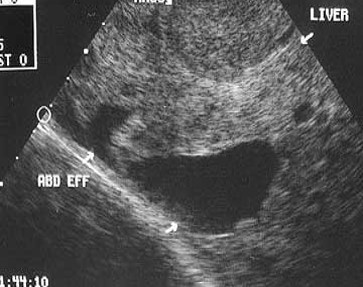

What is this?

Ultrasound confirmed the presence of free fluid in the abdomen